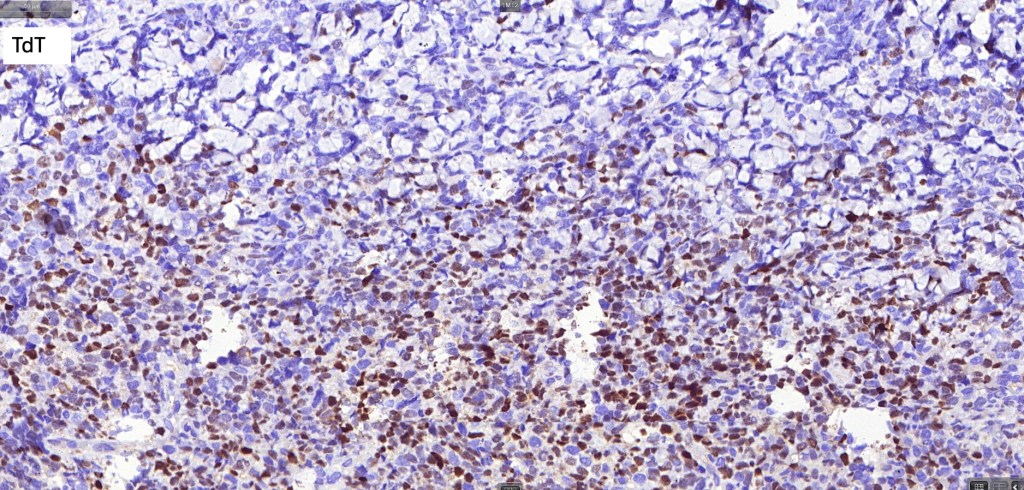

. Variable CD68, CD7, CD33 & TdT +ve